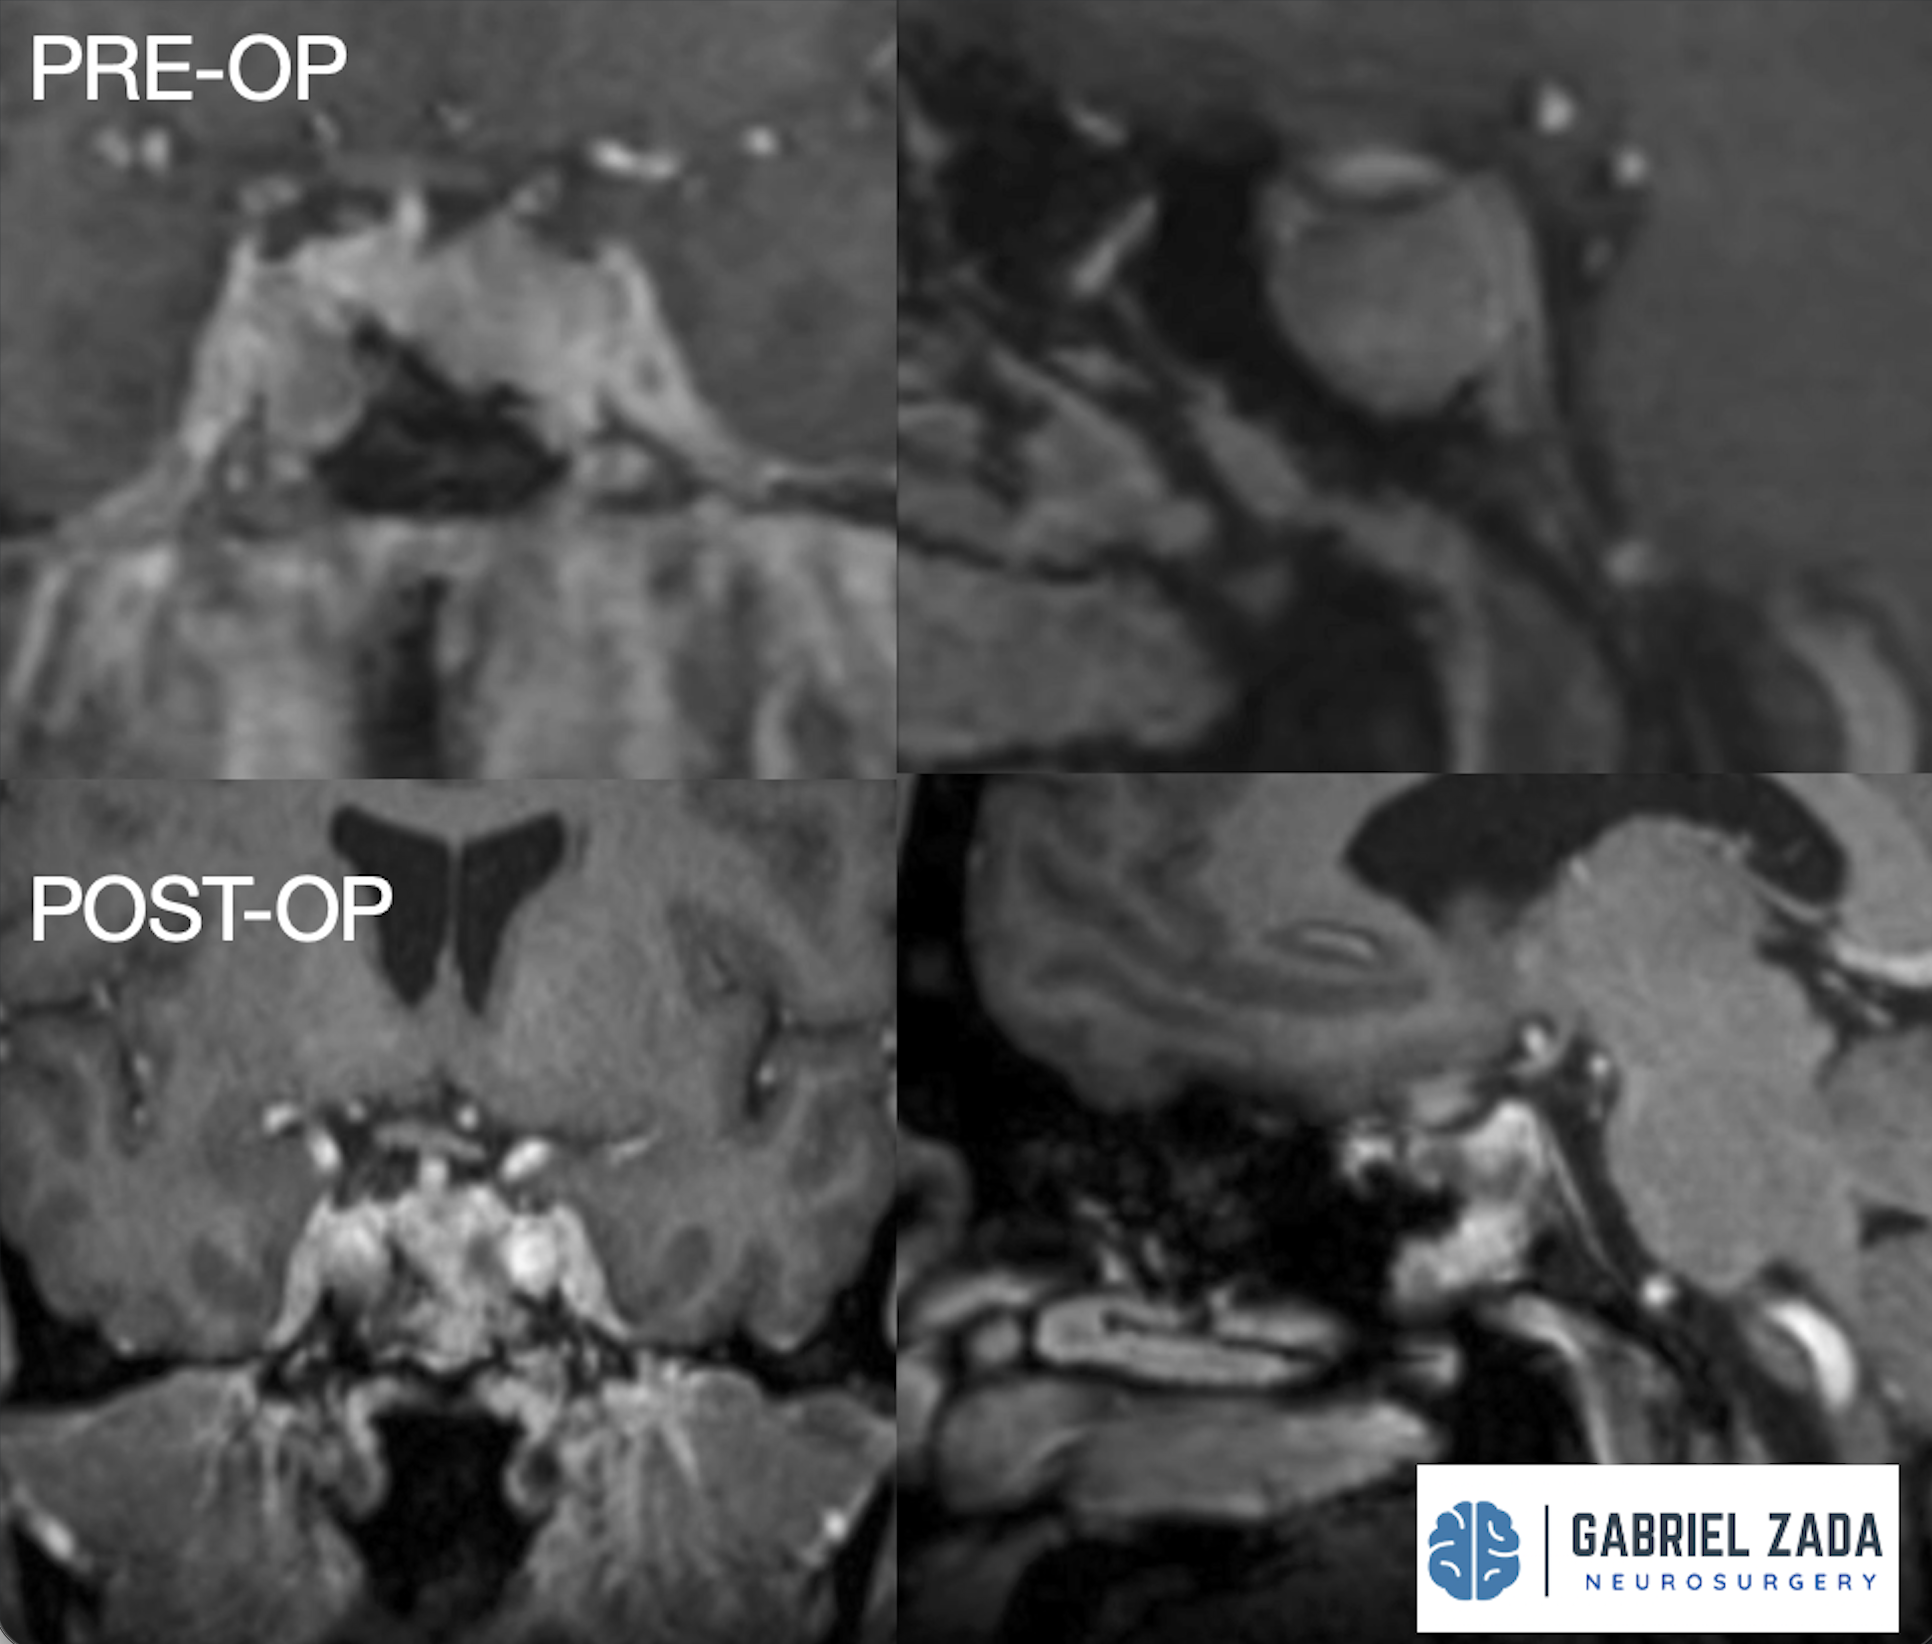

Explore this comprehensive gallery featuring pre‑ and post‑operative imaging of patients with skull‑base tumors treated by Gabriel Zada, MD, MS, FAANS, FACS. These cases highlight Dr. Zada’s expertise in advanced neurosurgical techniques and outcomes.

*Representative cases shown for educational purposes. All images de-identified. Individual results vary.